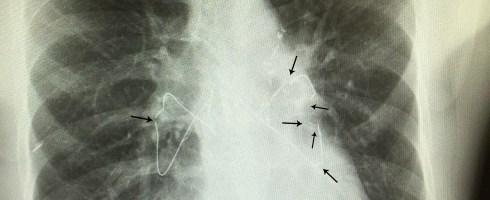

The list could go on and on. He’s had numerous ER visits and surgeries/procedures since his transplant. Remember the broken sternal wires he had to have removed? The bronchoscopy that caused a collapsed lung and need for chest tube and hospitalization? We know another surgery to remove more kidney stones is in his future. Despite all these things, Jody would say post transplant life is pretty good. If you’ve followed Jody’s story you know he’s not a complainer. He accepts his “issues” and doesn’t let them stop him; they pale in comparison to the issues his old CF lungs caused him.